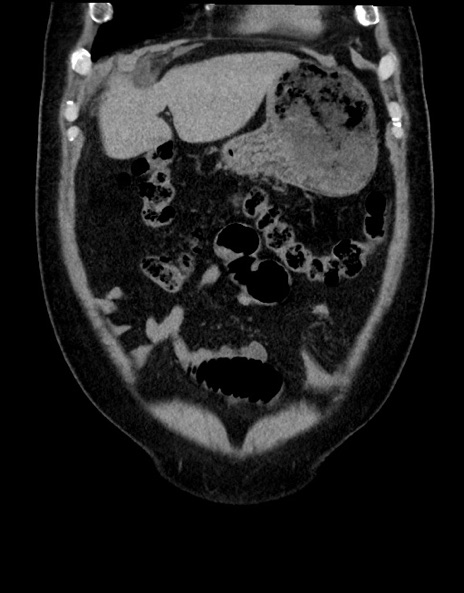

症例15(冠状断像)

【症例】70歳代男性

【主訴】腹痛

【現病歴】今朝から腹痛あり。全体的に痛い。特に左上の方。排ガスが今日はない。冷や汗が出る。

【既往歴】直腸癌術後

【身体所見】左側腹部〜上腹部に圧痛あり。腹膜刺激症状明らかなではない。軽度反跳痛。左下腹部に術後瘢痕あり。

【データ】WBC 7700、CRP 0.02